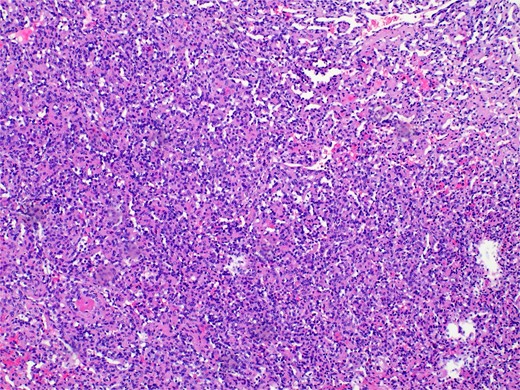

Pathology revealed a benign vascular neoplasm, whose morphological pattern favored AH (Figs 3 and 4).

Histopathology micro findings showing anastomosing proliferation of capillary-sized vessels with mild endothelial cell nuclear variability.

The name derives from its unique histological characteristics, characterized by blood vessels resembling capillaries organized in a unique anastomosing pattern. The cells lining up the vessels are generally uniform, with minimal atypia and mitotic activity. These cells may also exhibit a “hobnail” morphology, associated with some malignant tumors, including renal cell carcinoma.